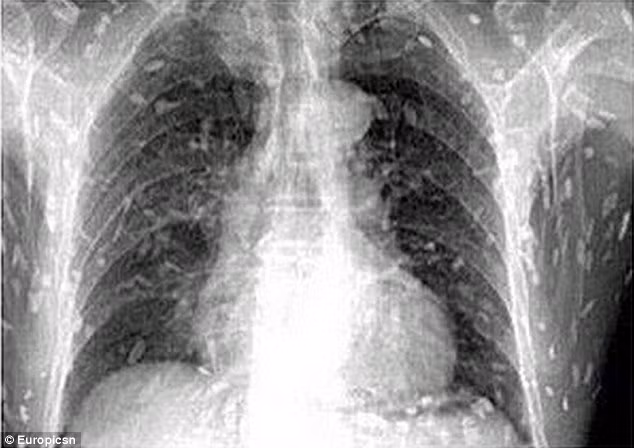

Phim chụp X-quang cho thấy sán dây làm tổ trong khắp cơ thể người đàn ông.

Kết quả chụp X-quang khiến anh chàng kinh hoàng thấy toàn bộ cơ thể mình bị nhiễm sán dây sau khi ăn quá nhiều sashimi – món cá sống cắt lát.